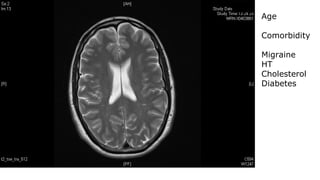

Periventricular, white matter lesions

Age

Comorbidity

Migraine

HT

Cholesterol

Diabetes